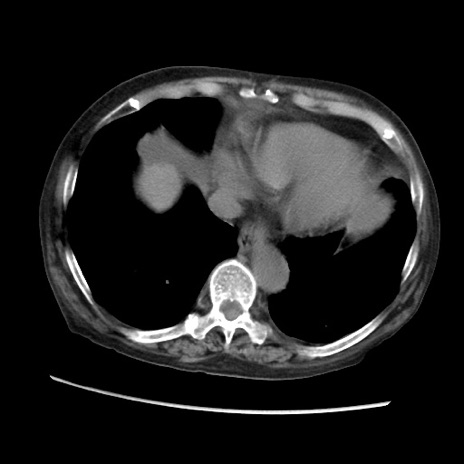

症例31(横断像)

【症例】80歳代 女性

【主訴】腹部膨満感

【現病歴】他院にて肝硬変にてフォロー中。1週間前から便秘、腹部膨満感、臍部腫瘤あり受診となる。

【既往歴】肝硬変

【身体所見】腹部膨隆あり、皮膚変化なし、疼痛なし。